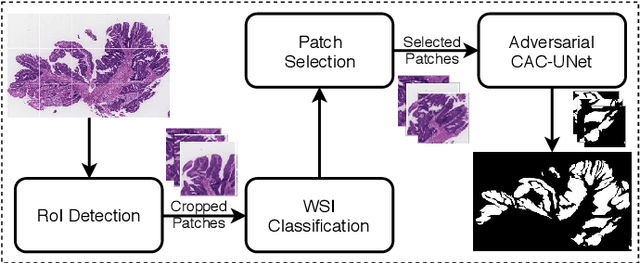

Multi-level colonoscopy malignant tissue detection with adversarial CAC-UNet

The automatic and objective medical diagnostic model can be valuable to achieve early cancer detection, and thus reducing the mortality rate. In this paper, we propose a highly efficient multi-level malignant tissue detection through the designed adversarial CAC-UNet. A patch-level model with a pre-prediction strategy and a malignancy area guided label smoothing is adopted to remove the negative WSIs, with which to lower the risk of false positive detection. For the selected key patches by multi-model ensemble, an adversarial context-aware and appearance consistency UNet (CAC-UNet) is designed to achieve robust segmentation. In CAC-UNet, mirror designed discriminators are able to seamlessly fuse the whole feature maps of the skillfully designed powerful backbone network without any information loss. Besides, a mask prior is further added to guide the accurate segmentation mask prediction through an extra mask-domain discriminator. The proposed scheme achieves the best results in MICCAI DigestPath2019 challenge on colonoscopy tissue segmentation and classification task. The full implementation details and the trained models are available at https://github.com/Raykoooo/CAC-UNet.